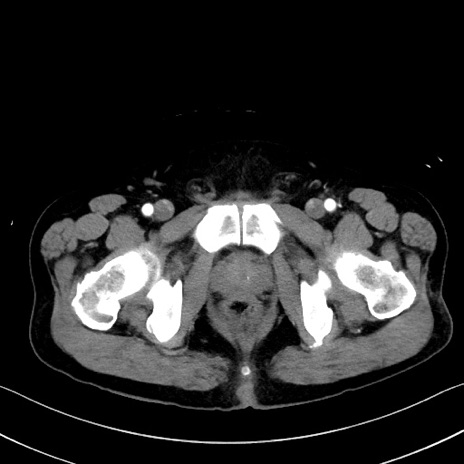

症例35(横断像)

【症例】70歳代 男性

【主訴】腹部膨満、嘔吐

【現病歴】昨日より腹部膨満感出現。本日増悪し、仙痛出現。嘔吐あり、受診。

【既往歴】糖尿病、胆摘後

【身体所見】BP 149/80mmHg、HR 74/min、BT 35.9℃、腹部:膨満、軟、圧痛なし。腸雑音減弱あり。上腹部正中切開瘢痕あり。

【データ】WBC 13500、CRP 1.72